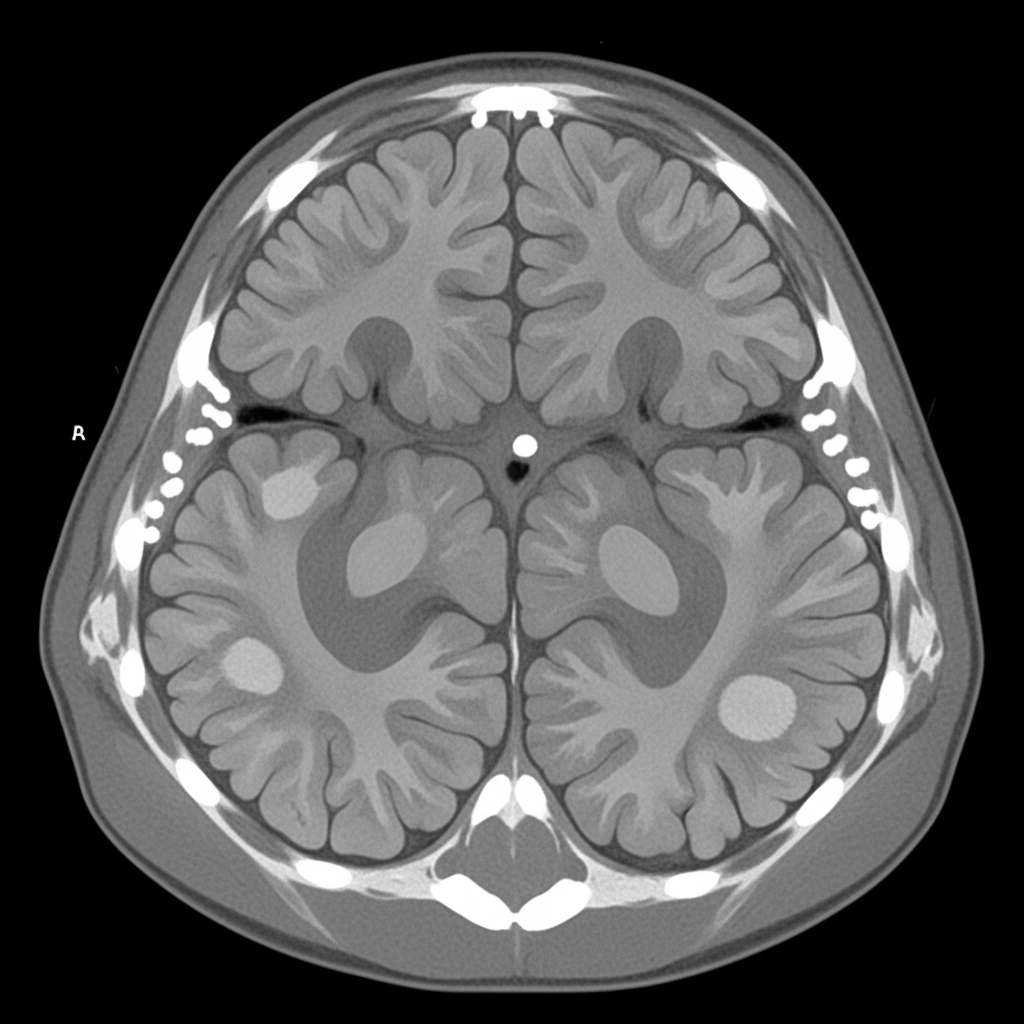

Explanation: ***Tuberous sclerosis*** - The combination of **mental retardation** (intellectual disability) and **skin rash on the cheeks** (adenoma sebaceum) forms part of the classic triad of tuberous sclerosis. - CT scan typically shows **subependymal calcified nodules** (candle-guttering appearance) and **cortical tubers**, which are pathognomonic findings. *Von Hippel-Lindau disease* - Primarily characterized by **retinal angiomas** and **cerebellar hemangioblastomas**, not skin rashes on cheeks. - Associated with **renal cell carcinoma** and **pheochromocytoma**, but intellectual disability is not a typical feature. *Sturge-Weber syndrome* - Features a **port-wine stain** (capillary malformation) typically in the **trigeminal nerve distribution**, not a rash on cheeks. - CT shows **tramtrack calcifications** in the occipital cortex, not subependymal nodules. *Ataxia-telangiectasia* - Characterized by **progressive cerebellar ataxia** and **telangiectasias** on bulbar conjunctiva and skin creases. - Associated with **immunodeficiency** and increased cancer risk, but facial rashes are not typical presentations.

Explanation: **Explanation:** Hydrocephalus is characterized by an imbalance between cerebrospinal fluid (CSF) production and absorption. **Non-communicating (obstructive) hydrocephalus** occurs when there is a physical blockage within the ventricular system, preventing CSF from reaching the subarachnoid space. **1. Why "Congenital Anomaly" is Correct:** Congenital malformations are the most frequent cause of obstructive hydrocephalus in the pediatric population. Among these, **Aqueductal Stenosis** (narrowing of the Aqueduct of Sylvius) is the single most common specific cause. Other congenital triggers include the Dandy-Walker malformation and Chiari malformations. **2. Analysis of Incorrect Options:** * **Perinatal injury:** While intraventricular hemorrhage (IVH) in premature infants is a major cause, it more frequently leads to *communicating* hydrocephalus due to blood products obliterating the arachnoid villi, though post-hemorrhagic clots can occasionally cause acute obstruction. * **Post-inflammatory obstruction:** Conditions like neonatal meningitis can cause adhesions. While significant, these typically result in communicating hydrocephalus due to basal cistern fibrosis. * **Brain tumors:** While a common cause of *acquired* obstructive hydrocephalus (e.g., medulloblastoma blocking the 4th ventricle), they are statistically less common than congenital structural defects in the overall pediatric age group. **NEET-PG High-Yield Pearls:** * **Most common cause overall:** Aqueductal stenosis (Non-communicating). * **Dandy-Walker Malformation:** Characterized by triad of cystic dilation of the 4th ventricle, cerebellar vermis hypoplasia, and enlarged posterior fossa. * **Clinical Sign:** "Setting-sun" eye phenomenon (downward gaze palsy due to pressure on the midbrain tectum). * **Macewen’s Sign:** "Cracked pot" sound on percussion of the skull due to separated sutures.